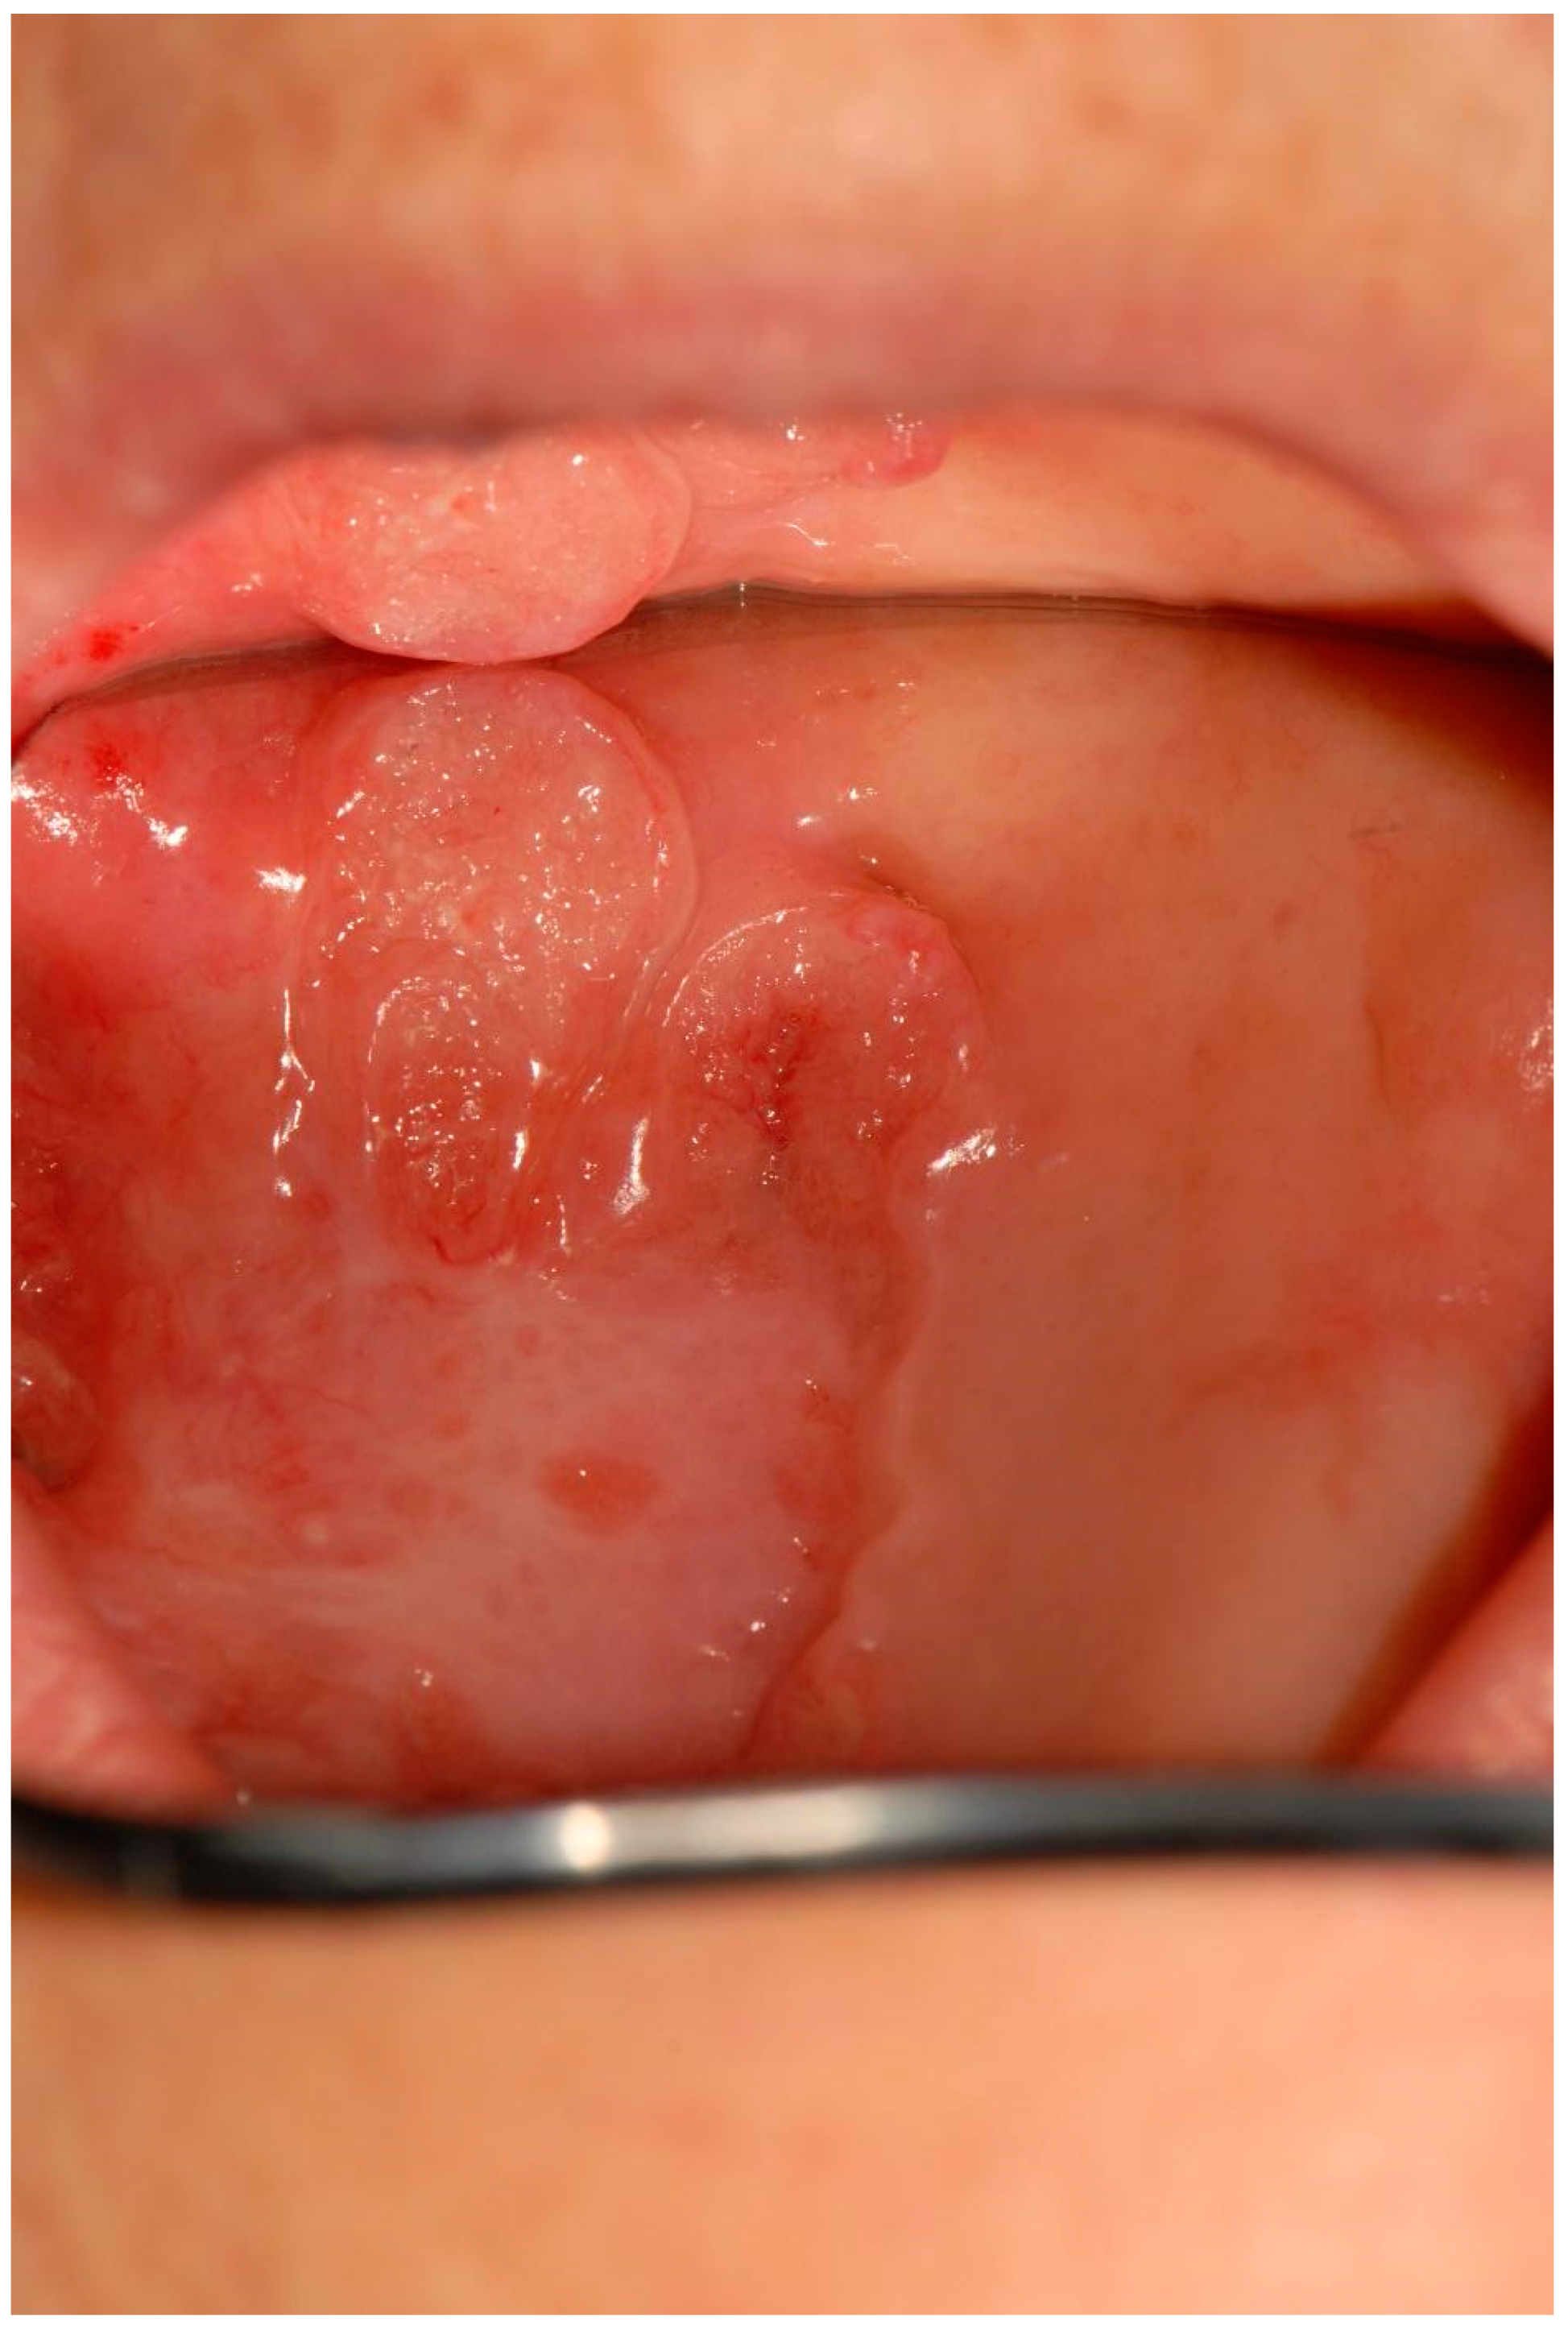

| 4 | Removable whitish plates Erythematous area Xerostomia | Candidiasis (pseudomembranous candidiasis, median rhomboid glossitis) | Dorsal tongue Oral mucous membranes | Nystatin Mucosamin® mouthwash | 3rd dose 9th dose |

| 6 | Non-removable whitish lesions | Hyperkeratosis | Palate Cheek mucosa | Aminogam® mouthwash | 4th dose |

| 7 | Non-removable white lesions | Hyperkeratosis | Dorsal tongue Palate | Aminogam® mouthwash | 3rd dose |

| 12 | Non-removable whitish lesions | Epithelial atrophy and hyperkeratosis without dysplasia | Cheek Dorsal tongue | Aminogam® mouthwash | 4th dose |

| 13 | Erythematous area Ulcer Removable whitish plates | Epithelial atrophy without dysplasia Ulcer Candidiasis | Palate Tuberosity Dorsal tongue Alveolar process | Nystatin | 2nd dose 4th dose |